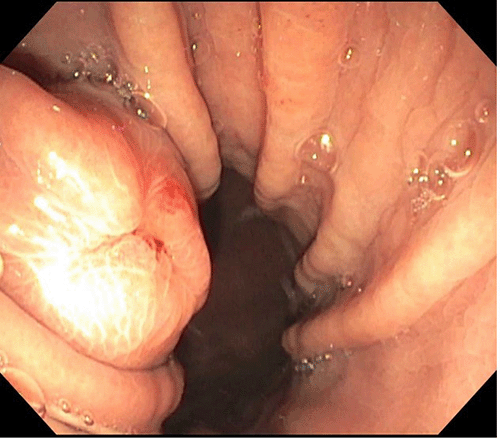

Upper GI endoscopy demonstrating exophytic nature of the lesion and location on lesser curvature of stomach.

To better characterize the mass, the patient was referred for upper GI endoscopy. The study demonstrated a subepithelial lesion on the lesser curvature of the stomach with an area of central umbilication. The patient also underwent endoscopic ultrasound (EUS), which showed a 3.5 × 3.2 cm, hypoechoic, multicystic, septated mass (Figure 2). The lesion appeared to originate from the muscularis propria with well-defined borders. Multiple biopsies were taken, and tissue was sent for pathologic interpretation. Immunohistochemistry (IHC) was performed, which stained positive for CD31 and negative for c-KIT, PDGFR, and DOG-1. CD31 positivity suggested this to be a highly vascular lesion as CD31 is an endothelial cell marker. The lack of expression of c-Kit, PDGFR, and DOG-1 made our presumptive diagnosis of a GIST less likely. Importantly, staining for S-100 was not performed at this juncture. Thus, the working pathological diagnosis was gastric hemangioma. The mass, however, did not appear to have the physical characteristics of hemangioma during endoscopic visualization. Given the size and the endoscopic characterization of the mass, the decision was made to offer the patient surgical resection of the lesion without a definitive diagnosis.